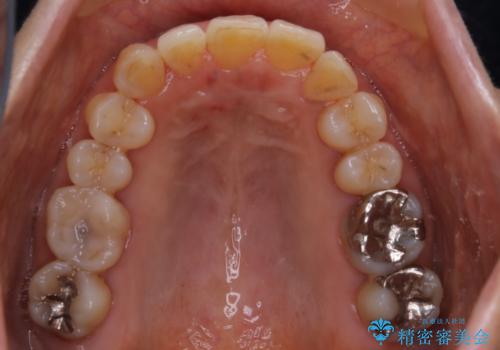

- 上下の歯のがたつきと、噛み合わせが深いことを気にされてご相談にいらした方です。噛み合わせに参加していない歯を抜歯してインビザラインにて治療を行いました。

一般的に噛み合わせの深い方へのインビザライン治療は適応が難しいとされていますが、今回は噛む力を上手にコントロールできたことと、内側に入り込んでいた前歯の角度を調整したことで下の歯がしっかり見えるようになりました。短期間で劇的に見た目が改善し、大変喜んでいただけました。